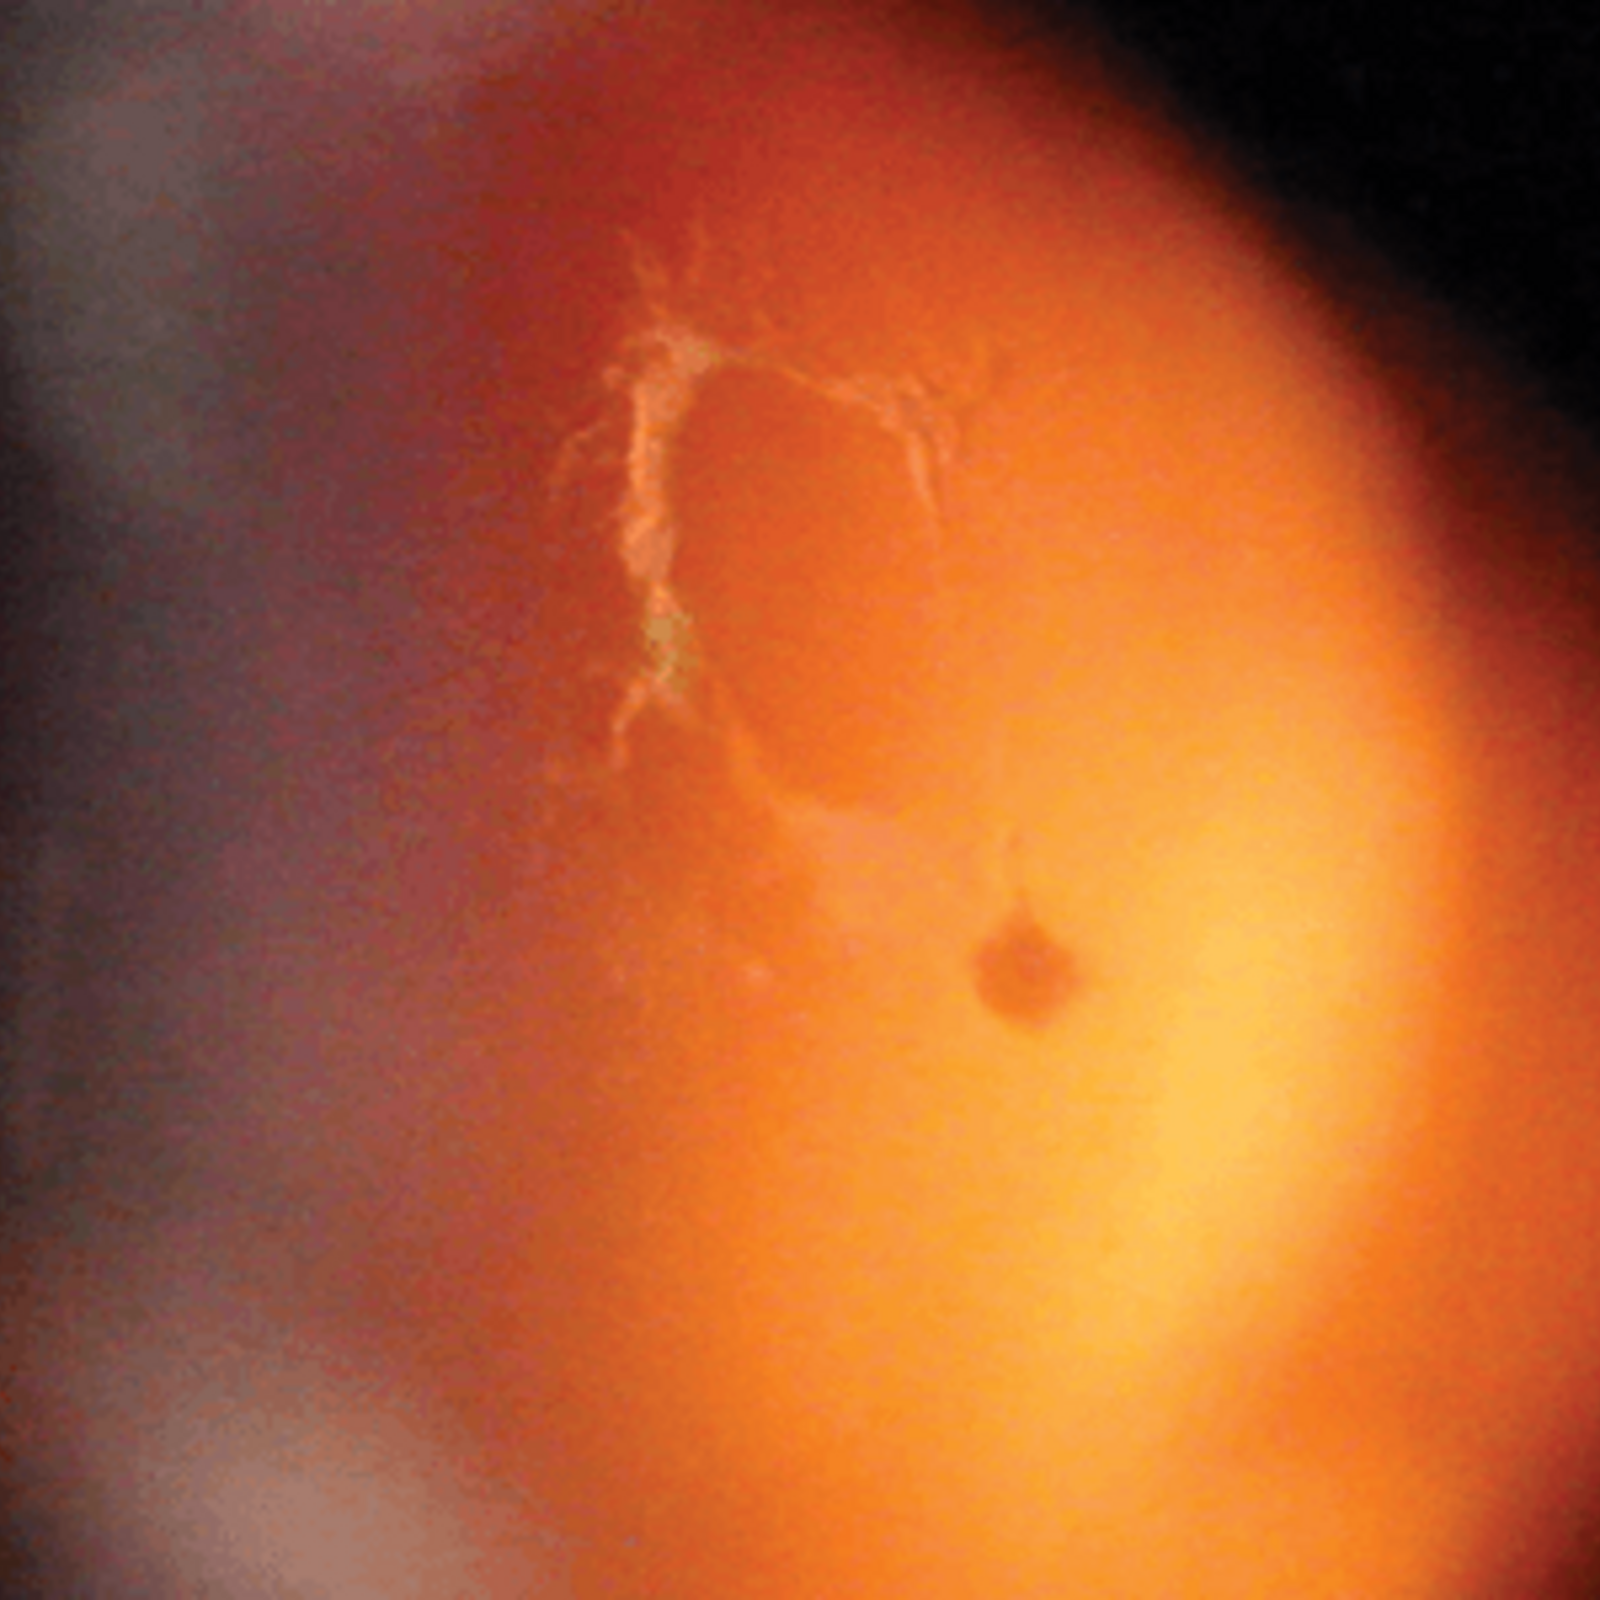

我們視物就像目光透過一個金魚缸,如果水變得混濁,就會看到有半透明東西在眼前飄浮,這就是飛蚊症了。當玻璃體老化時會變得混濁,便會出現飛蚊症狀,若因玻璃體老化萎縮而撕扯到視網膜,視線就會出現閃光,像有人在用閃光燈拍照一般。如果視網膜因此而破洞,飛蚊症狀會急劇增加,也會出現閃光視覺,一旦有這些狀況發生,就要盡快求醫做眼科檢查,若然置之不理視網膜可能會完全脫落,導致視力驟降,或周邊視野有黑影,彷似戲院落幕一樣,嚴重甚至眼前有大片黑影,造成不可逆轉的視力缺失或失明。

如果只是玻璃體老化,與視網膜分離是毋須手術治療的,只需持續觀察視網膜有沒有破損情況,即使有飛蚊症狀亦屬正常。若不幸發現視網膜破洞,就要進行激光治療修補。病情惡化至視網膜剝落的話,治療手術會更複雜,若液體流到黃斑點,部分視力損傷即使手術也不能逆轉,所以盡早求醫非常重要。